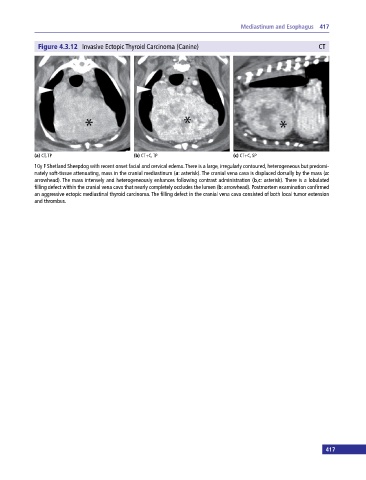

Figure 4.3.12 Invasive Ectopic Thyroid Carcinoma (Canine) CT

(a) CT, TP (b) CT+C, TP (c) CT+C, SP

10y F Shetland Sheepdog with recent onset facial and cervical edema. There is a large, irregularly contoured, heterogeneous but predomi

nately soft‐tissue attenuating, mass in the cranial mediastinum (a: asterisk). The cranial vena cava is displaced dorsally by the mass (a:

arrowhead). The mass intensely and heterogeneously enhances following contrast administration (b,c: asterisk). There is a lobulated

filling defect within the cranial vena cava that nearly completely occludes the lumen (b: arrowhead). Postmortem examination confirmed

an aggressive ectopic mediastinal thyroid carcinoma. The filling defect in the cranial vena cava consisted of both local tumor extension

and thrombus.